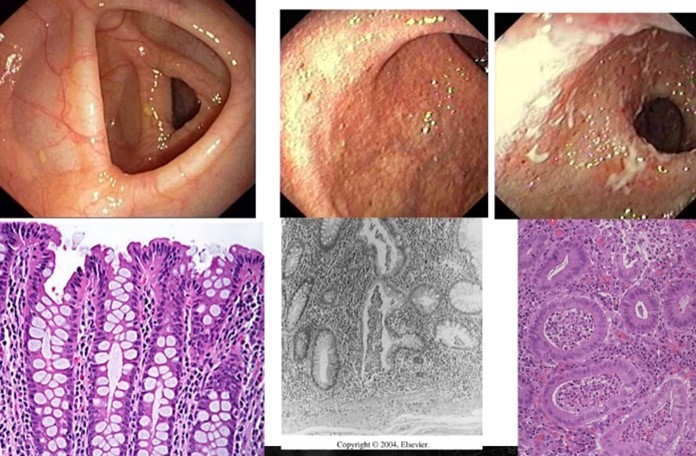

Vilken sjukdom och vad ses?

Crohns sjukdom med ett granulom

- Transmural inflammation

- Sårbildning

- Granulom

- Kryptabcesser

När kan detta ses vid mikroskopisk bild?

Crohns

Vad visar bilden och vad kan sjukdomen ge upphov med tiden?

- Utvekling av Crohns stegvis, startar till vänster med ett litet fibrinbelagt sår

- Kan ge upphov till fistelgång till hud

- Försnävning i tarm (väggens tjocklek ökar)

- Fett till tarmkexet kryper upp och kan baka in tunntarm ex

- Ge krökningar i tarm så mat kan fastna (liksom fibrinsbelagda sår)

Vilken sjukdom och vad visar bilden?

- Ulcerös kolit

- Till vänster friskt

- Mitten ödem bildas i mukosa (reflexer och sytrådarna borta

- Höger – sårbildning med fibrinbeläggning, eventuellt faller mukosa av

- Kan också ge stenos till slut, peristaltiken slutar fungera

Vilken sjukdom och vad är speciellt med sjukdomen i förhållande till bilden?

Ulcerös kolit

- Skarp gräns mellan normal och sjuk bit